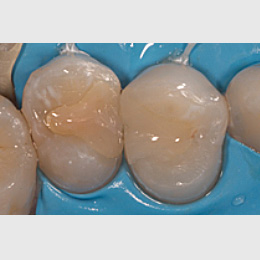

Fallbeispiel: Revision 46 (und 45) Recall 6 Monate

Bringt eine Wurzelkanalbehandlung nicht den gewünschten Erfolg, bedeutet dies nicht, dass ein Zahn nicht mehr zu erhalten ist. Mit einer Revisionsbehandlung können auch bereits wurzelkanalbehandelte Zähne langfristig erhalten werden!